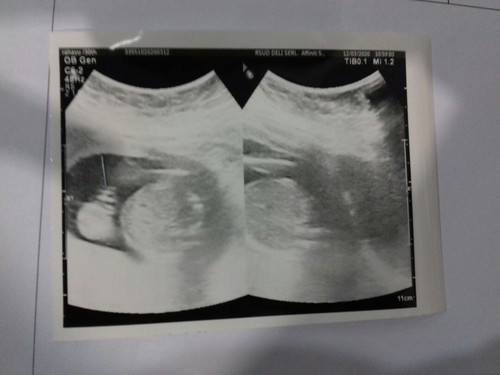

Hasil usg

Alhamdulillah hari ini habis kontrol terakhir pasca pengobatan sifilis.. aku langsung di anter sm perawat2 baik ke dr.obgyn untuk lihat perkembangan anak ku, alhamdulillah tadi udah liat anakku. Dan aku sudah tau jenis kelaminnyaaa?.bahagia campur sedih,walau td detak jantung nya sempat melemah.. langsung di cek dr lagi dan alhamdulillah sdh normal kembali,, kata dr utk skrg ini semua normal dan mudah2an sampai lahir ttp normal..Aamiin! Dan dikasih dokter vitamin..

ratu of 2 enerjik 1 raja